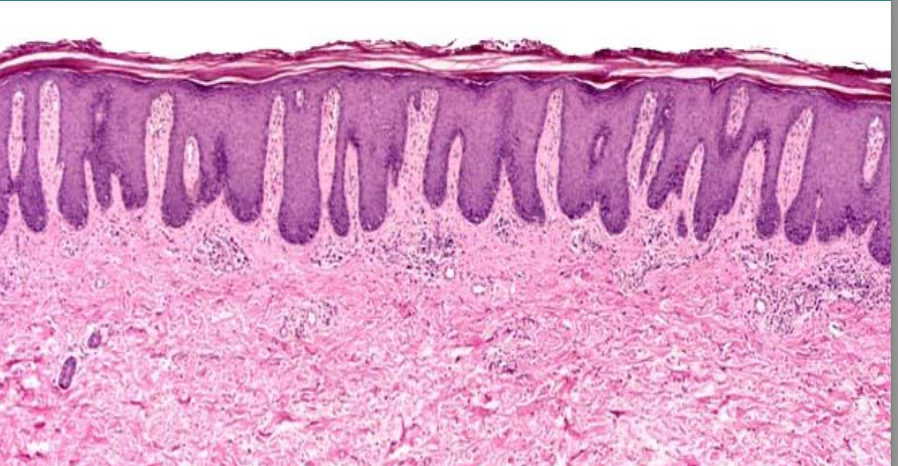

8

A

Psoriasis: acanthosis and parakeratosis